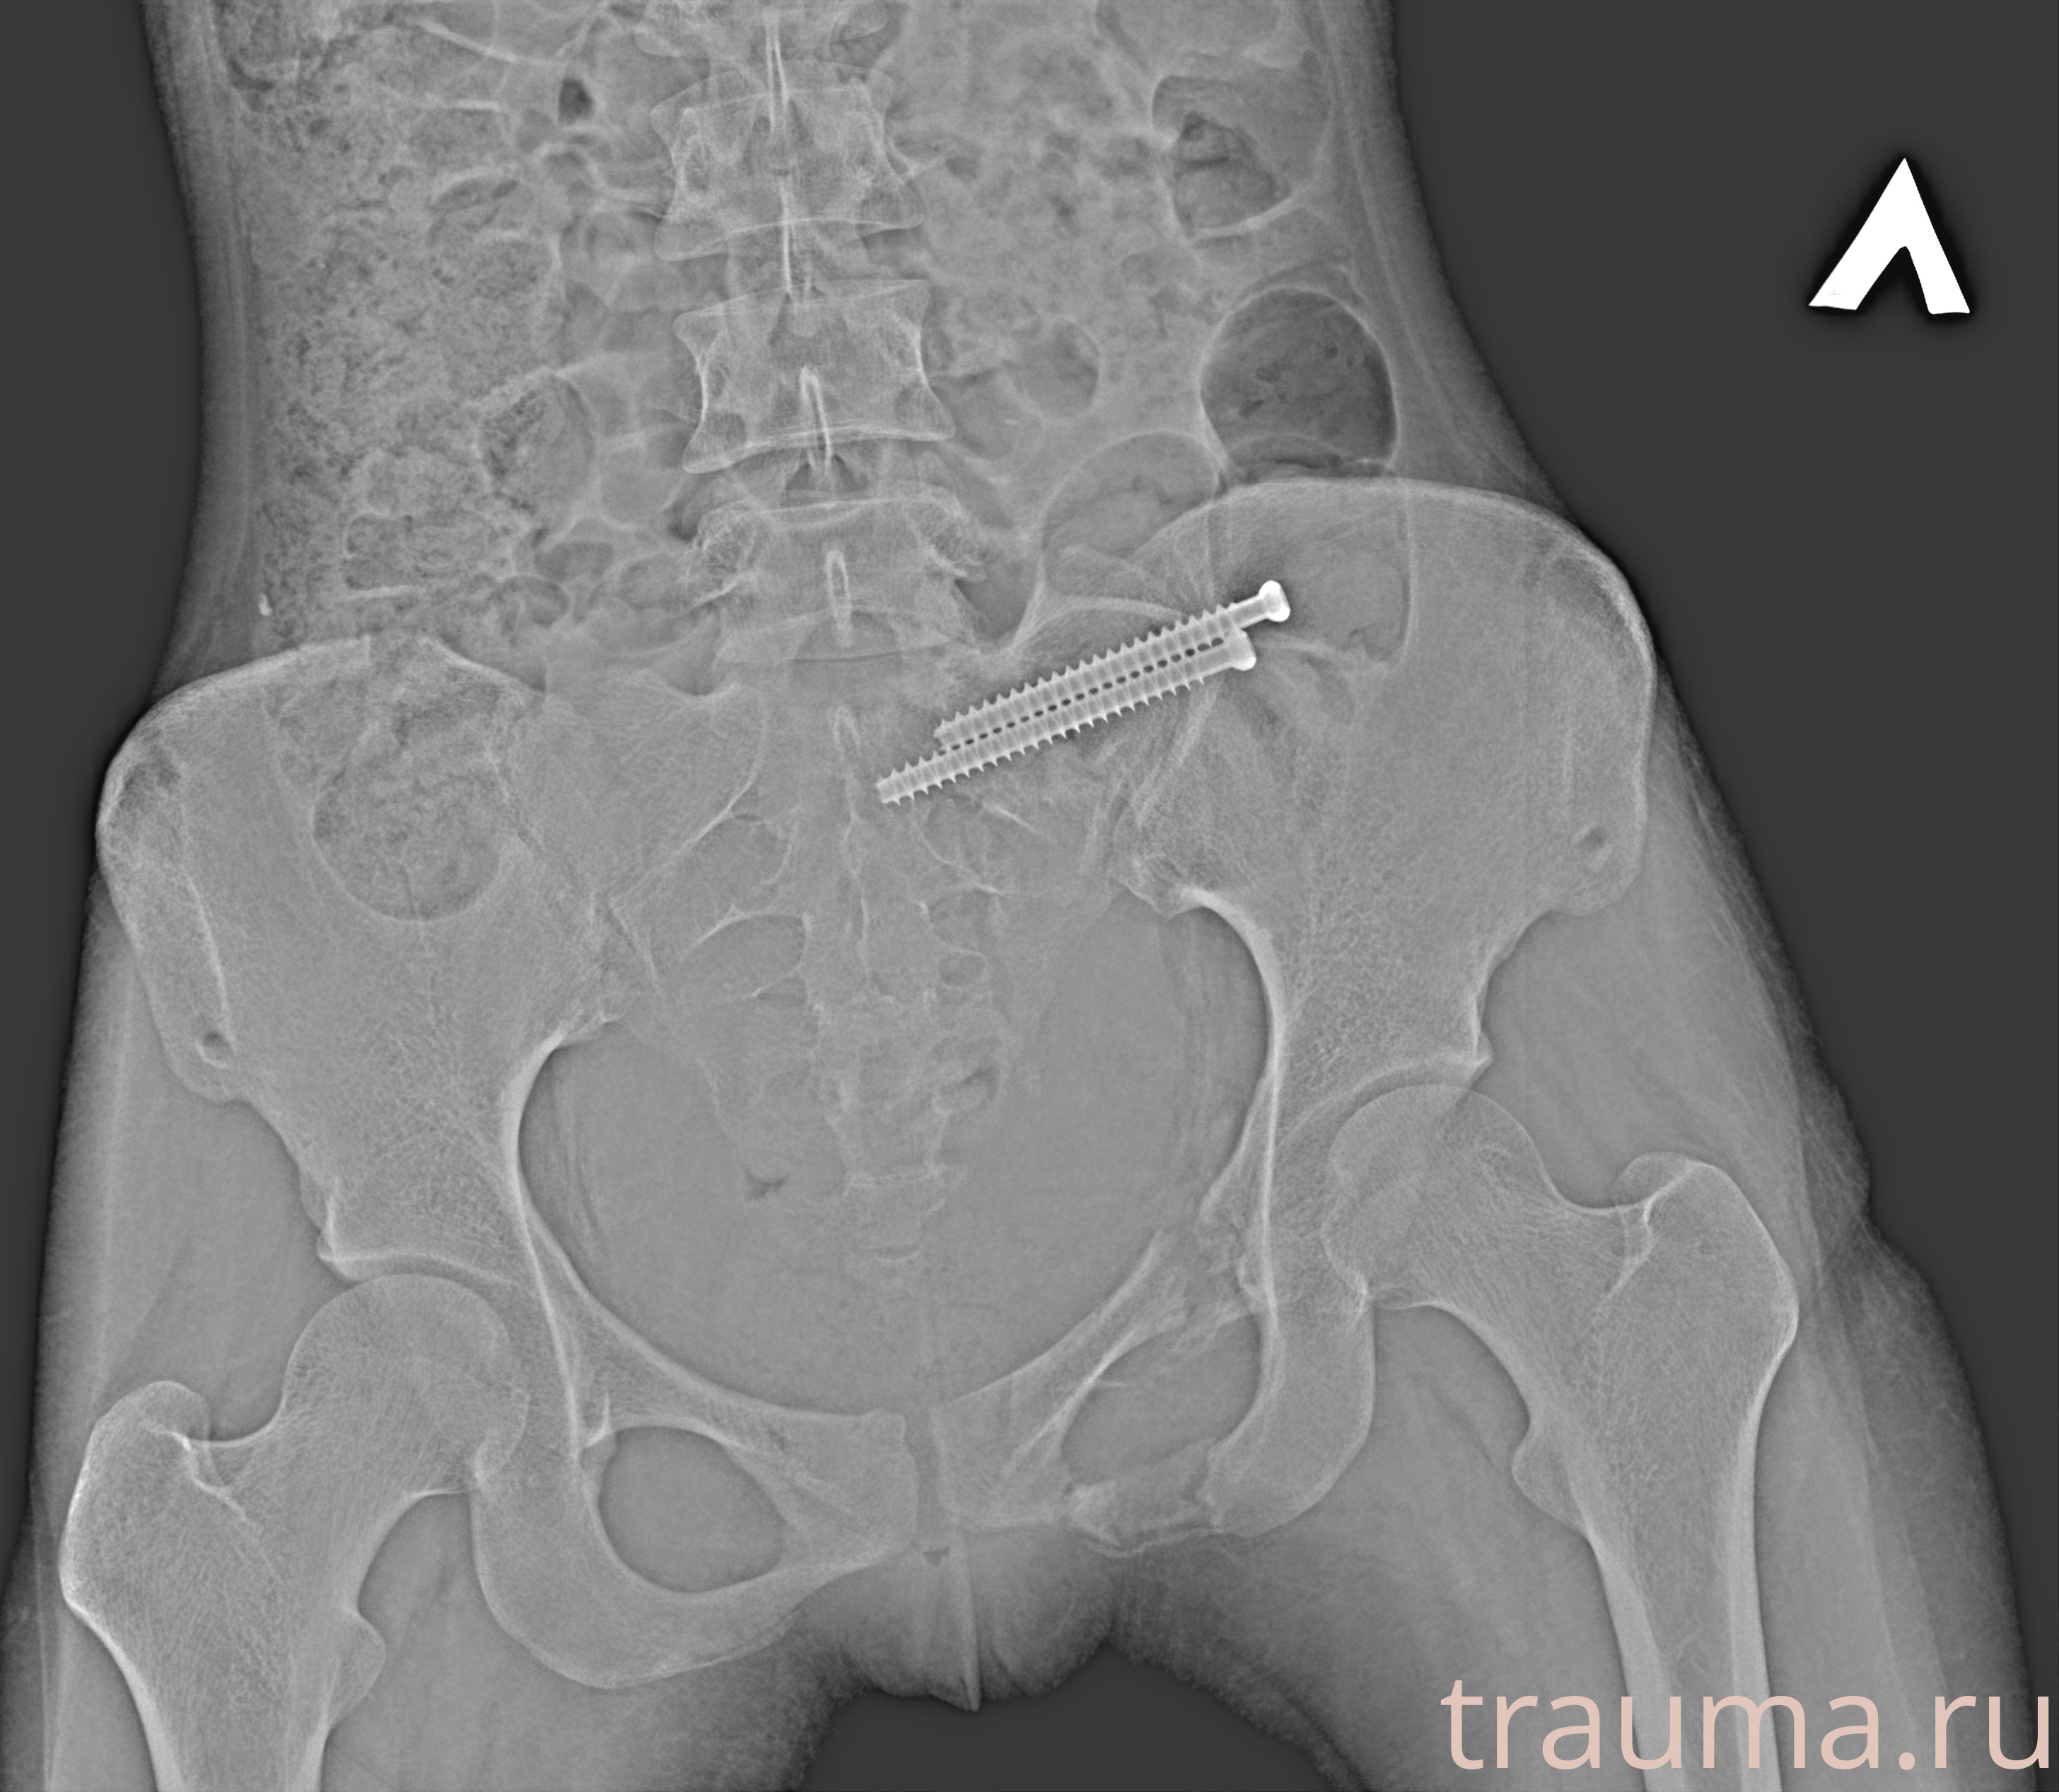

Рентгенограммы